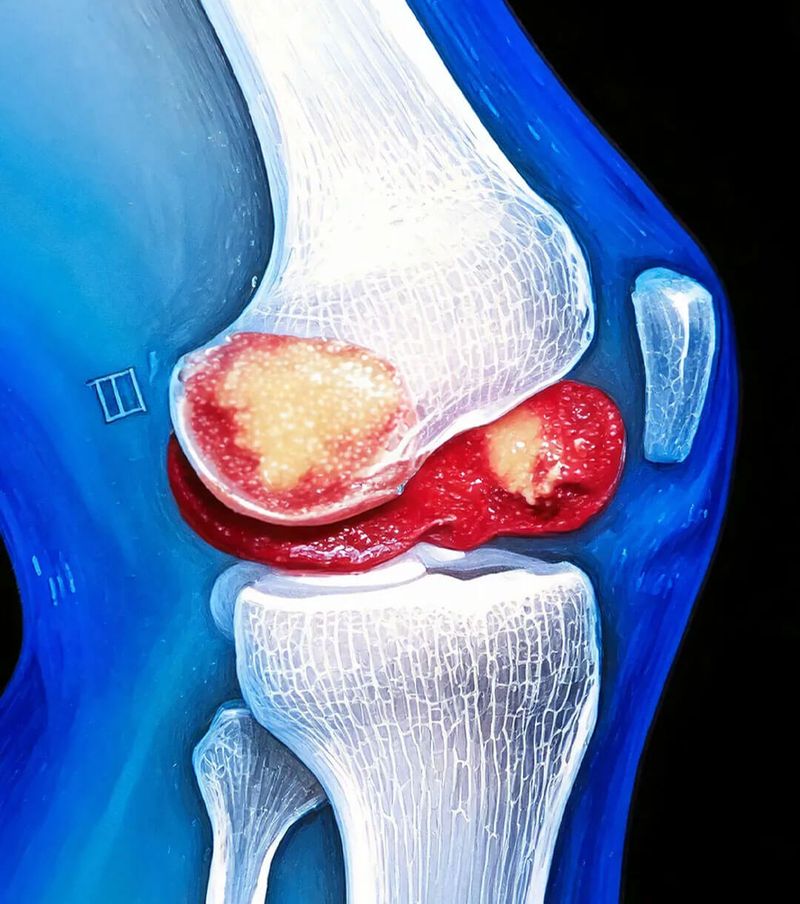

De menopauze is meer dan alleen een periode van verandering. Het beïnvloedt vrijwel elk proces in je lichaam – vaak met gevolgen die pas geleidelijk aan duidelijk worden. Vooral je gewrichten worden in deze periode getroffen. Een belangrijke reden hiervoor is de zogenaamde afvalbarrière dat zich in de gewrichten vormt. Maar wat betekent dit precies en hoe ontwikkelt dit zich?

X-Factor afvalbarrière: wanneer je gewricht een valkuil wordt

Onder normale omstandigheden reinigt je lichaam zichzelf.

Bij elke beweging, ontstaan afvalproducten in onze gewrichten - vergelijkbaar met hoe een motor uitlaatgassen produceert wanneer deze draait.

Deze microscopisch kleine deeltjes hopen zich op in de gewrichtsruimte en kunnen ontstekingen en pijn veroorzaken.

In gezonde toestand worden deze afvalstoffen afgevoerd door de synoviale vloeistof.

Maar tijdens de menopauze verandert de samenstelling van deze vloeistof!

Het resultaat:

De afvalproducten blijven in het gewricht achter en irriteren het gevoelige weefsel. Na verloop van tijd ontstaat er een vicieuze cirkel van ontstekingen en verdere afzettingen.

Tijdens de menopauze, functioneert dit systeem plotseling niet meer zoals het hoort.

In plaats daarvan, stapelen de afvalproducten zich op, als een sediment in de gewrichten.

Ze vormen een echte barrière - vergelijkbaar met een verstopt filter.

Deze "afvalbarrière" heeft twee problematische gevolgen:

Enerzijds veroorzaakt het zelf irritatie en ontstekingen.

Aan de andere kant blokkeert het de weg voor belangrijke voedingsstoffen die het gewricht dringend nodig heeft voor zijn herstel

De gewrichten worden als het ware van twee kanten aangevallen - ze kunnen geen afvalproducten verwijderen en ook geen nieuwe voedingsstoffen opnemen.

Deze belasting zorgt ervoor dat je gewrichten pijn doen, stijf worden en sneller slijten.